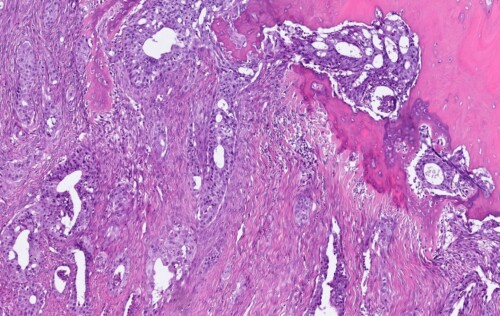

Photos 6 à 8 : Examen histopathologique du doigt.

Prolifération tumorale de nature épithéliale, nettement carcinomateuse, peu différenciée. Elle revêt une architecture lobulaire et plus rarement tubuleuse. Elle est associée à un stroma fibroplasique

abondant. Les cellules néoplasiques sont de grande taille, arrondies à polyédriques, à cytoplasme éosinophile étendu. Les noyaux sont arrondis, volumineux, plutôt vésiculeux, fortement mono ou ou plurinucléolés. L’anisocaryose est nette. L’activité mitotique est élevée. Absence d’images nettes d’embolisation vasculaire. La prolifération tumorale infiltre largement les tissu mous le long des phalanges (Photos Antech LAPVSO)